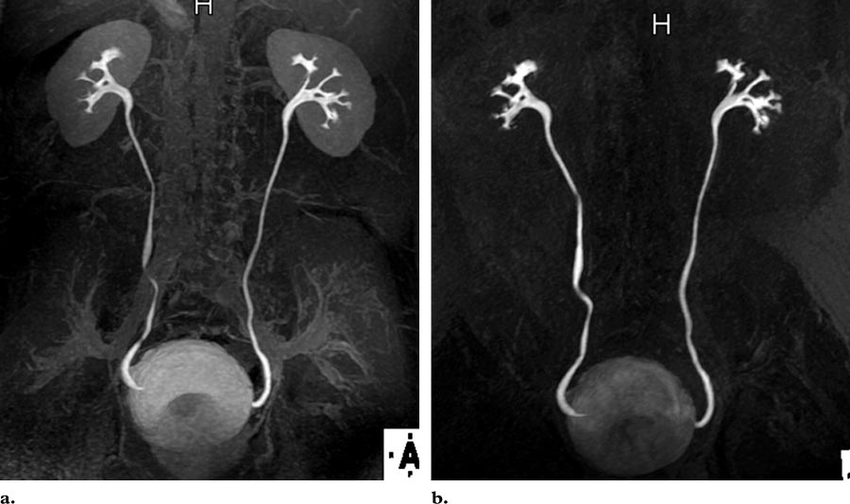

Экскреторная урография позволяет оценить эффективность работы почек, а также всей выделительной системы. Контрастный раствор, проходя через фильтрационную систему почечных канальцев, остается неизменным, он хорошо виден на рентгеновском снимке. По тому, где находится контраст через определенное время после введения, судят об экскреторной функции почек.

Целью исследования служит определение следующих патологий:

- почечнокаменная болезнь;

- гидронефроз;

- травмы почек;

- опухолевые процессы в почках как доброкачественного, так и злокачественного характера;

- дивертикулез, деформации мочевого пузыря;

- туберкулез почек;

- врожденные патологии почек и органов выделительной системы.

Интерпретация результатов урографии осуществляется урологом. На основании изучения снимков он дает заключение о состоянии почек и других органов выделительной системы, в котором описывает выявленные отклонения от нормы. Экскреторная урография показывает:

- анатомическое положение, структуру почек;

- состояние чашечно-лоханочного аппарата почек, его структуру, форму;

- состояние мочеточников по отдельности и в сравнении, их размеры, анатомическое положение, деформации, скорость продвижения по ним контрастного вещества;

- состояние мочевого пузыря, его размеры, локализацию, характеристики стенок.